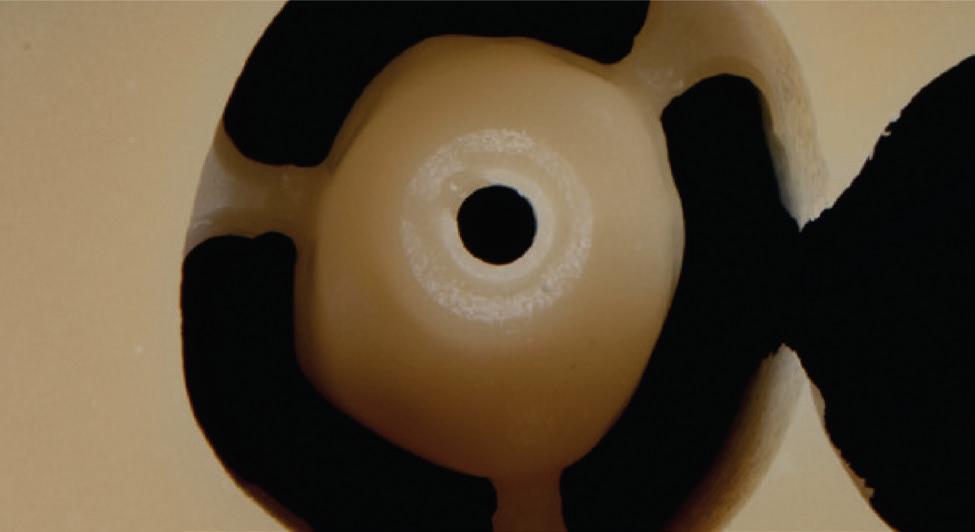

Traditional dental implants use a titanium post that fuses directly to the jawbone to support a ceramic crown, and the surgery often cuts or damages nearby nerves. To tie these inert pieces of metal into the body’s sensory system, the Tufts team developed an implant wrapped in an innovative biodegradable coating. This coating contains stem cells and a special protein that helps them multiply and turn into nerve tissue. As the coating dissolves during the healing process, it releases the stem cells and protein, fueling the growth of new nerve tissue around the implant.

The coating also contains tiny, rubbery particles that act like memory foam. Compressed so that the implant is smaller than the missing tooth when it’s first inserted, these nanofibers gently expand once in place until the implant snugly fits the socket. This allows for a new minimally invasive procedure that preserves existing nerve endings in the tissue around the implant.